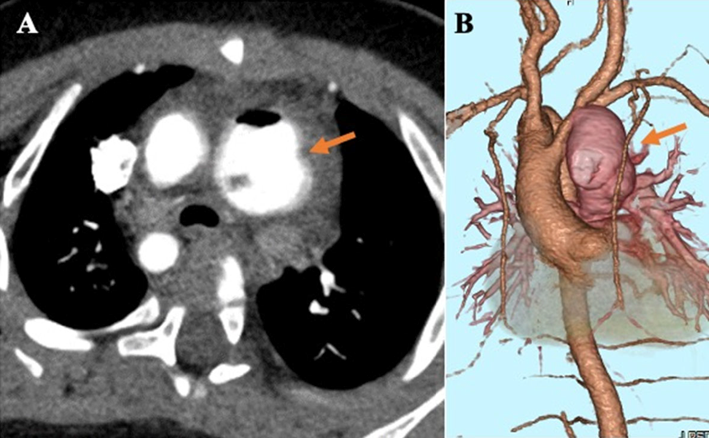

【心臓超音波検査】mBTシャント周囲に退院前エコーでは認めなかった血液の流入を伴う管腔構造を認めた(Fig. 1).

Fig. 1 Subxiphoid view on echocardiography

A luminal structure with blood inflow was observed around the modified Blalock–Taussig shunt (arrow), although it was not observed on the echocardiogram which was performed before discharge.